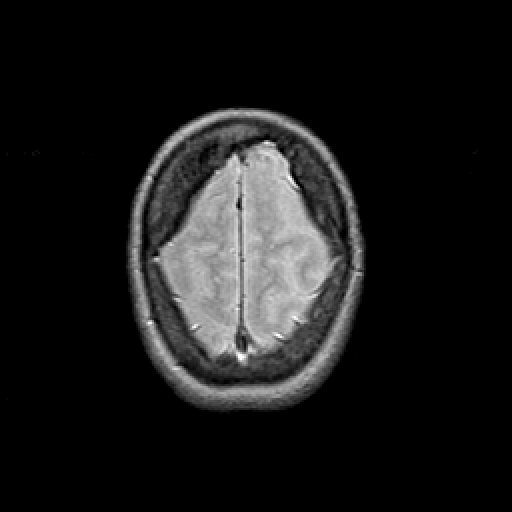

Proton density-weighted structural MR: Slice 46

Slice 46